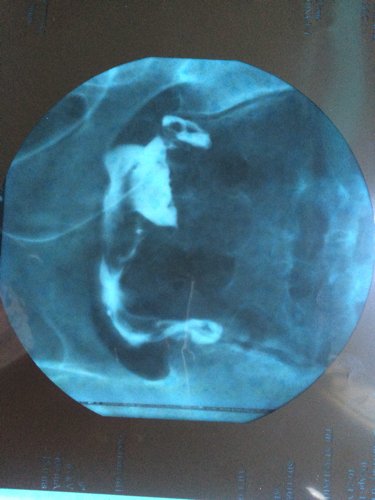

麻烦看看图,检查结果显示双侧输卵管通畅,但是医生看了片说通畅得不好,很难自然怀孕,要求做宫腔镜手术 麻烦看看图,检查结果显示双侧输卵管通畅,但是医生看了片说通畅得不好,很难自然怀孕,要求做宫腔镜手术,这什么情况呀? 点击展开 494317348 2015-05-01 18:51 为您推荐: 其他回答 通畅。建议在两次月经之间那几天爱爱比较容易受孕。还要检查男方是不是精子也正常才行。 匿名用户 2015-05-01 20:09 准备坑你钱了 匿名用户 2015-05-01 19:01 这是手术里面的 匿名用户 2015-05-01 18:52 相关问题 请问做宫腔镜检查都是好的!输卵管口也是清晰可见是不是说明输卵管也是通的?有图!麻烦懂的人帮忙分析一 怀孕五个月,发现右肾结石,医生建议保守治疗,建议多喝水自然排石,问题是如果长时间自然排石不成功对孕 我想问下医生如果子宫有炎症,怀孕了是不是查不出来,麻烦专业医生回答,谢谢